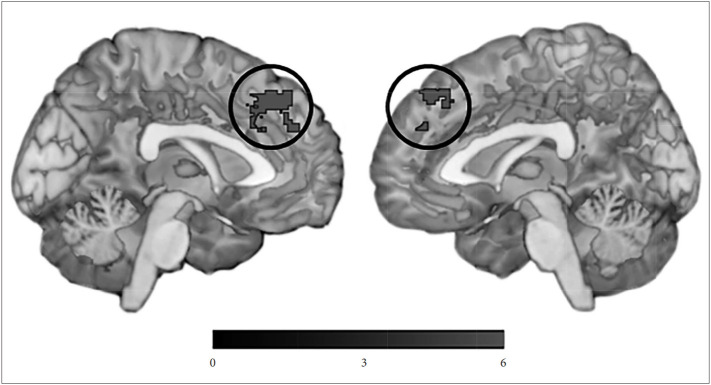

Hyperactivity subsyndrome score was negatively correlated with network measure of the left medical prefrontal cortex (MNI -4, 36, 46; 397 voxels; z=5.00) (Figure 1). Other NPS subsyndromes score did not show any significant correlation with network measure.

Figure 1.

Areas of negative correlation between default mode network and Hyperactivity syndrome.